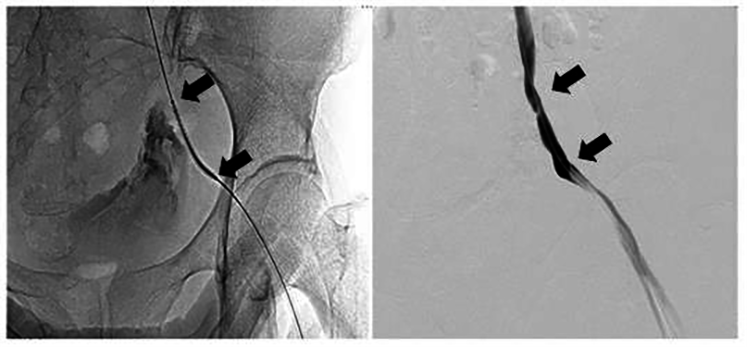

Internal jugular central venous catheterization, massive blood transfusion and

drugs administration were done as an emergency exploratory interventional

surgical was performed simultaneously. Bilateral renal artery angiography showed

no vascular anomalies and contrast spillover. However, there was obvious contrast

agent spillover on the left external iliac artery (Fig. 2). The patient was

diagnosed with a ruptured left external iliac artery pseudoaneurysm. A covered

stent, measuring 8 mm

Fig. 2.Angiography showed obvious contrast agent overflow from ruptured pseudoaneurysm on the left external iliac artery (arrow).